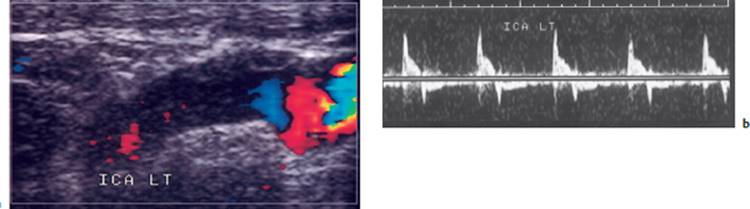

Fig. 4.26 Color-coded duplex ultrasonography of carotid stenosis. a Duplex ultrasonography of the carotid bifurcation. Rapid flow is coded as bright, slow flow as dark. Flow is abnormally rapid in the internal carotid a. (ICA) because the lumen is narrowed. Atherosclerosis can be seen in the thickened vessel wall (arrow). b Flow spectrum of the internal carotid a. showing elevated maximal systolic and end-diastolic velocities (from the laboratory of the Neurological and Neurosurgical Clinics, University of Berne, Switzerland). ECA = external carotid a., CCA = common carotid a.

Fig. 4.27 Color-coded duplex ultrasonography of an occlusion of the left internal carotid a. 3 cm above the carotid bifurcation. a Blood flow can be seen up to the bifurcation. In the internal carotid a. (ICALT), there is only minimal movement of the blood column. b Doppler ultrasonography reveals no more than a brief forward flow in early systole at greatly reduced maximal speed; backward flow is already seen in early diastole.

Fig. 4.27 c MR angiography reveals occlusion of the internal carotid artery.

Indications. The velocity and flow profile (laminar or turbulent) of the blood flowing within a particular vessel depend, among other things, on the vessel's caliber and on the nature of its wall. Ultrasound studies aid in the detection of vascular stenosis and occlusion, vessel wall irregularities, abnormalities of the speed and direction of blood flow, and turbulent flow. Insonation of the extra- and intracranial vessels (e.g., of the middle cerebral a. through the thin bone of the “temporal window,” or of the basilar a. through the foramen magnum) yields an informative picture of the current state of blood flow in the brain (Fig. 4.27). This diagnostic technique is inexpensive, non-invasive, and free of risk.